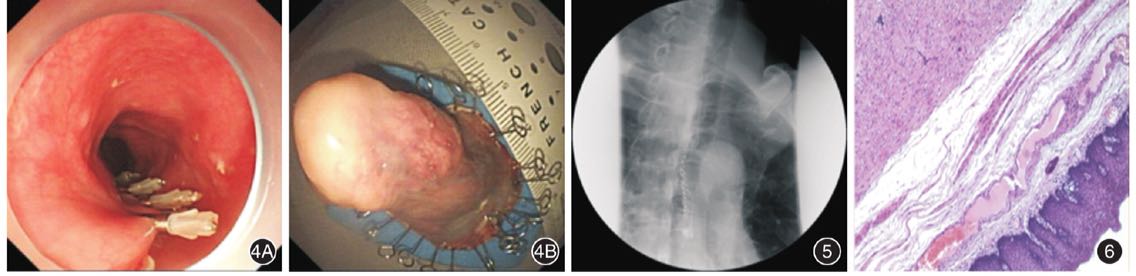

拟行全麻下ESD治疗,Dual刀标记边缘,甘油果糖、肾上腺素、亚甲蓝混合液黏膜下注射后抬举好,Dual自口侧开口,逐层剥离,完整切除病变,术闭钛夹夹闭创面,标本回收送病理(图4)。术后禁食禁水,予抑酸、预防感染及补液治疗。术后第3天食管泛影葡胺造影,食管中段可见多发金属影,造影剂通过食管各段顺利,未见明显造影剂外漏(图5)。病理回报:(距门齿28 cm)食管黏膜下梭形细胞肿瘤(图6)。免疫组化:Actin(+),Desmin(+),S-100(-),CD34(部分+),CD117(部分+),Dog-1(-),Ki-67(小于1%+)。病理结合免疫组化考虑为平滑肌瘤。

图4食管长蒂肿物的ESD治疗 4A:切除创面用钛夹夹闭;4B:切除的标本 图5ESD术后第3天食管泛影葡胺造影,食管中段可见多发金属影,造影剂通过食管各段顺利,未见明显造影剂外漏 图6ESD术后病理提示(距门齿28 cm)食管黏膜下梭形细胞肿瘤 HE ×10